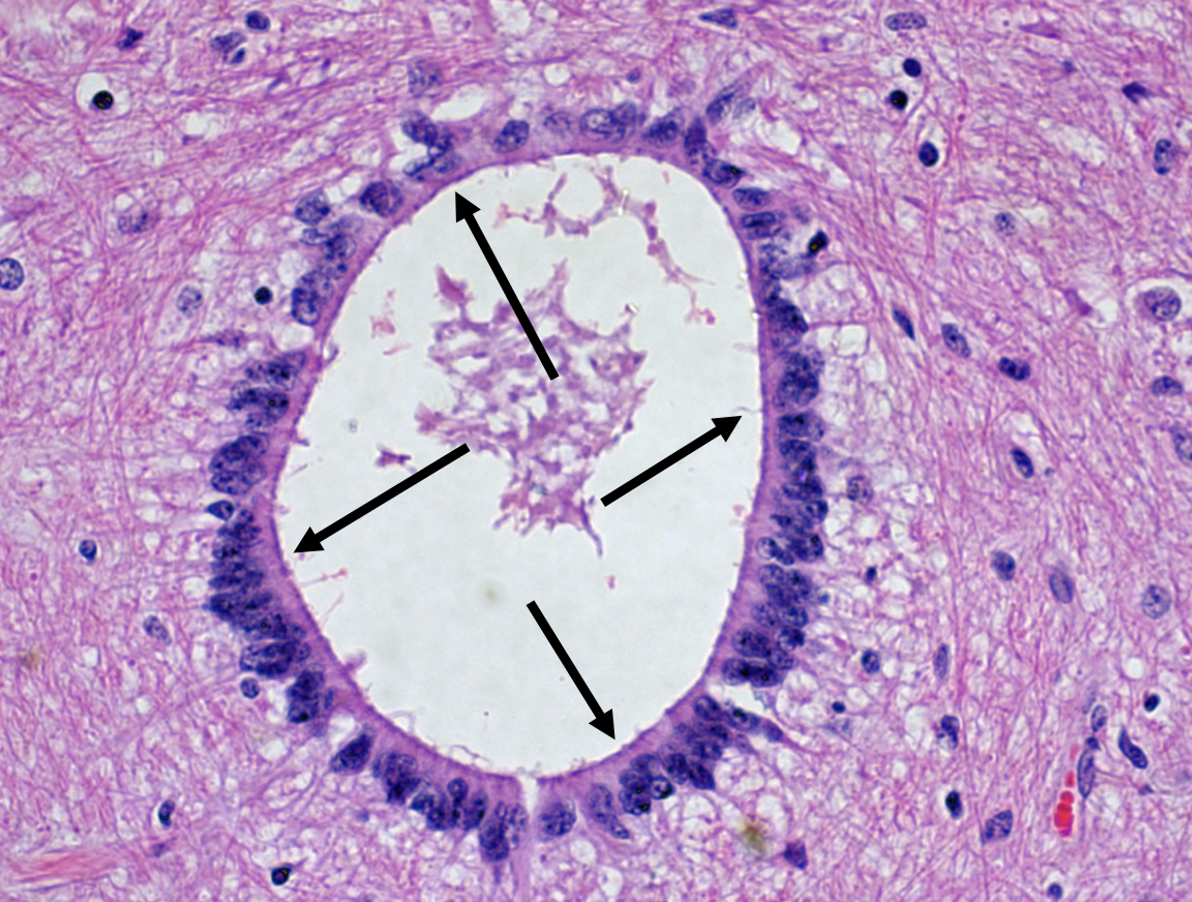

choroid plexus

Ependymal cells

Blue arrows --> arteriole tufts Black arrows --> ependymal cells